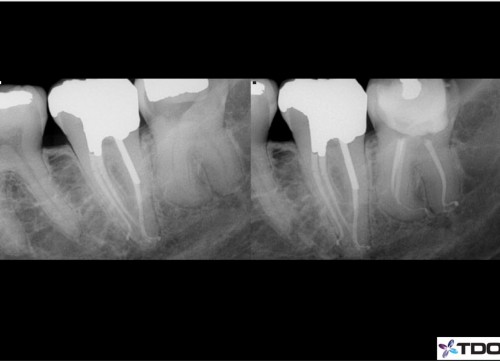

By Mark Dreyer / June 23, 2018

Treatment of complex third molar.  Second molar treated a few years prior.